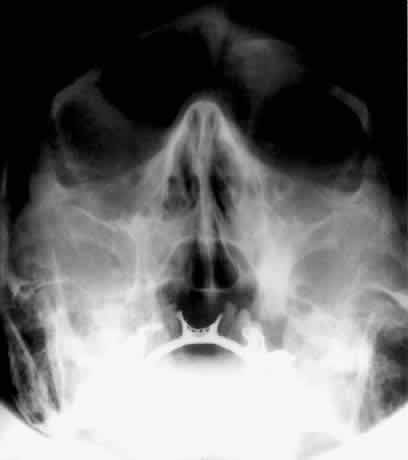

The optic foramen should measure 6 mm vertically and 5 mm horizontally. Asymmetry greater than 1 mm or a vertical dimension greater than 6.5 mm is considered abnormal.15,27 Ninety-eight percent of patients have optic canals that vary by less than 1 mm.27 Concentric enlargement of the foramen and optic canal can be seen with optic nerve gliomas, meningiomas, neurofibromatosis, and less commonly an aneurysm of the ophthalmic artery (Fig. 16). A decrease in the optic foramen and canal dimension can be seen in fibrous dysplasia, Paget's disease, hyperostosis secondary to a meningioma, or microphthalmos (Fig. 17, Table 1).

Fig. 17. Bilateral optic canal compression from fibrous dysplasia. There is diffuse bone thickening in each orbit. Note small size of optic foramen (arrow).